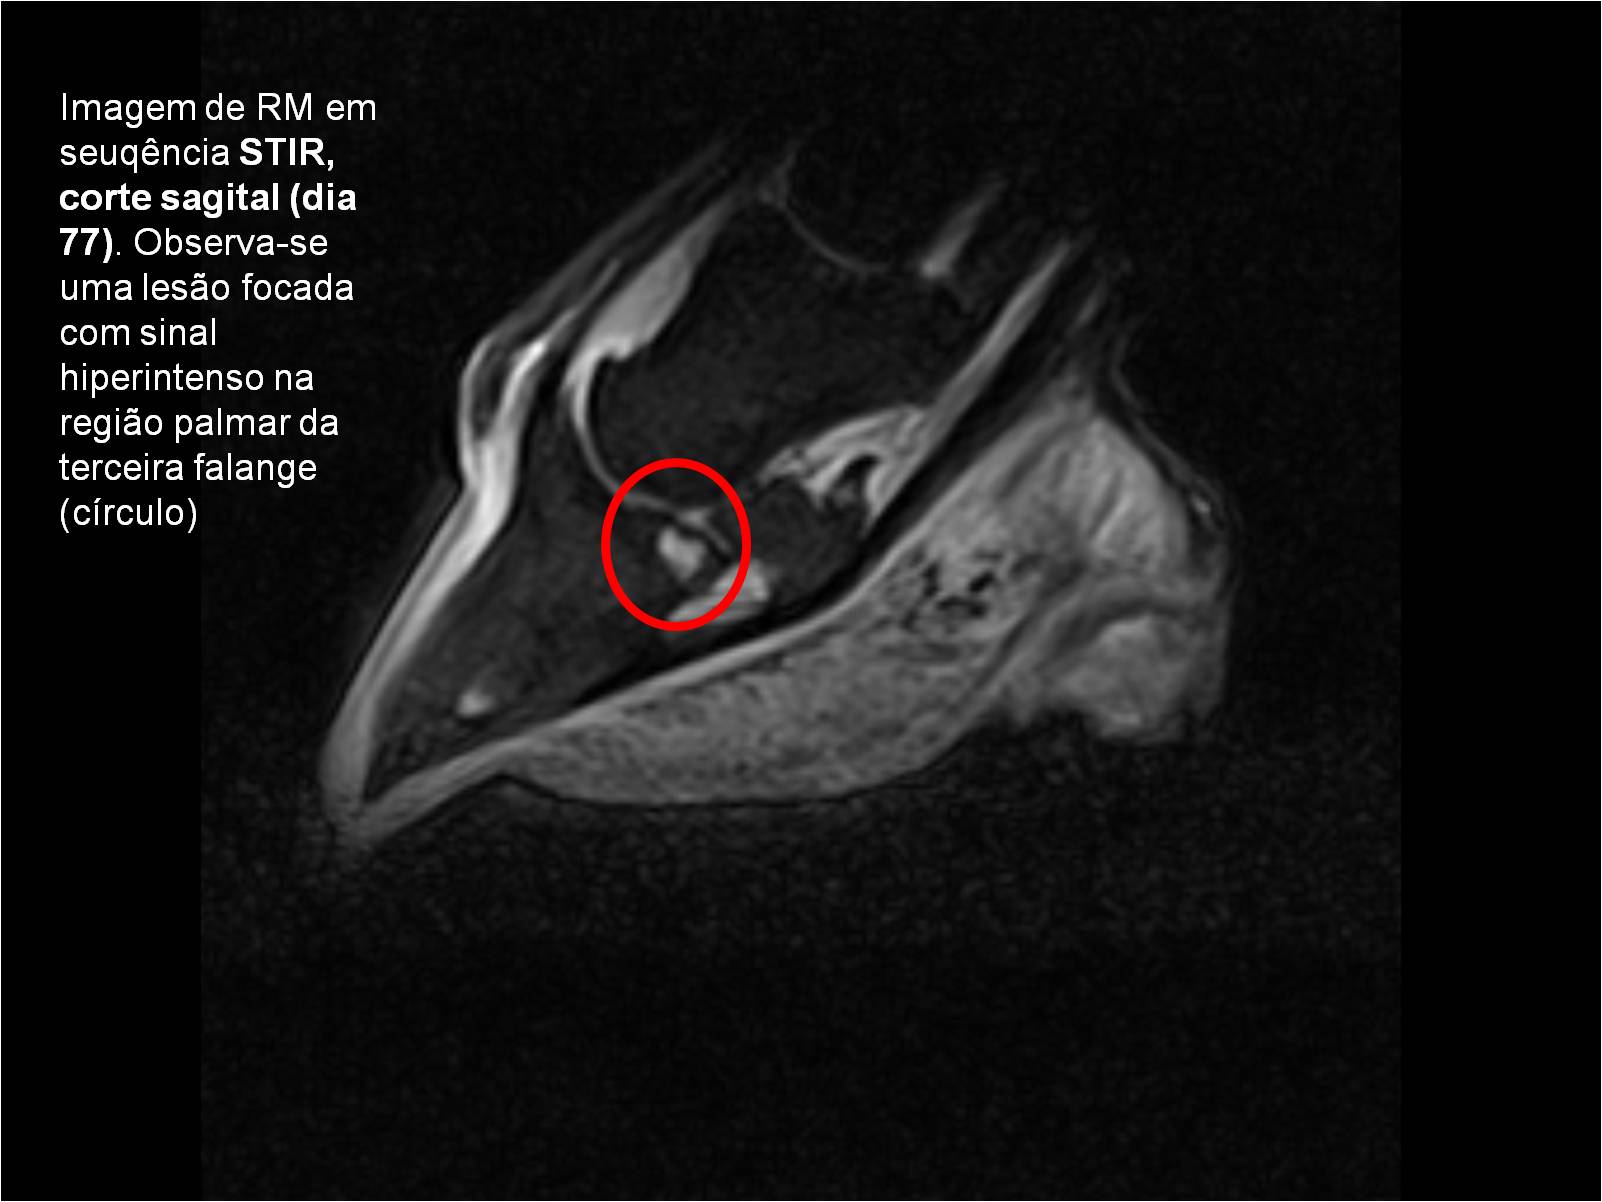

Publisher: Universidade de Évora

Abstract: O relatório de estágio encontra-se estruturado em três partes distintas. A primeira parte faz a caracterização das infraestruturas e funcionamento do Hospital Veterinário de Equinos de Lüsche, Oldenburg, Alemanha, assim como a análise casuística dos casos clínicos acompanhados durante os 6 meses de estágio. A segunda parte consiste de uma revisão bibliográfica sobre quistos do osso subcondral em equinos. Por fim, a terceira parte consta da apresentação e discussão de um caso clínico, nomeadamente o diagnóstico e acompanhamento imagiológico, por ressonância magnética, de um quisto subcondral na terceira falange num cavalo adulto; ### Abstract Equine Practice- Subcondral bone cyst of the third phalanx This internship report is divided in three parts. The first part characterizes the infrastructure and function of the Equine Hospital Lüsche, Oldenburg, Germany, as well as the casuistic of the clinical cases accompanied during the 6 month internship. The second part consists in a bibliographic review of cystic lesions of the subchondral bone in equines. The third part consists in a case report, the diagnostic and imagiological accompaniment, by use of magnetic resonance imaging, of a subchondral bone cyst in the distal phalanx of an adult equine.